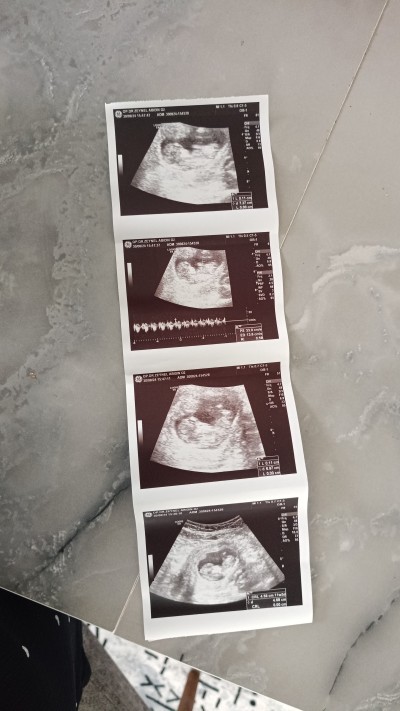

Merhabalar ikili testte erkek dendi 14+6 da baya zorlanarak bakti kiz dendi.detaylidada degisirmi ikisindede bacak arasina bakti erkek derken kordonu yandan geciyodu bacak arasi acikti yani karistirmamistir diye dusunuyorum ancak kafam cok karisti 12 ve en son goruntusunu birakiyorum tahminde bulunurmusunuz

Gebelik haftası 15

Bariz belli erkek cnmm